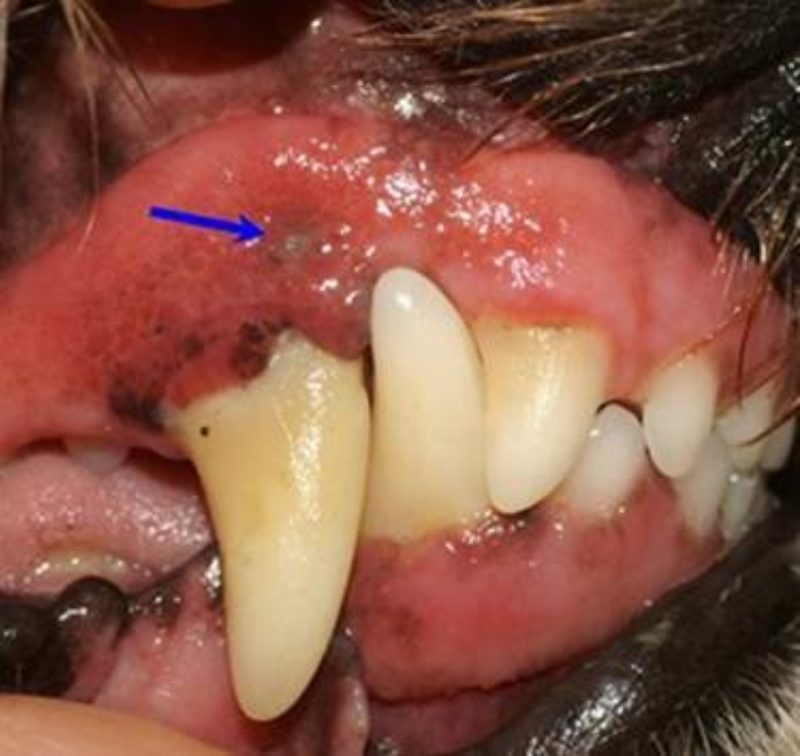

Als ich dann in meiner Praxis die vollständige Vorgeschichte aufnahm, berichtete Frauchen geradezu empört, dass sie nun etwa drei bis viermal pro Jahr im Hundesalon den Zahnstein habe abkratzen lassen, der Geruch aber geradezu immer stärker würde! Tatsächlich zeigte sich bei meiner ersten Untersuchung ein eigentlich nicht allzu starker Zahnsteinansatz (Bild 1 & 2). Bei genauer Betrachtung sah man allerdings zwischen den Zähnen Eiter hervorquellen, und der Gestank beschlug mir fast die Brille! Wo kam das her?

Bereits die sorgfältige Untersuchung des Zahnfleisches zeigte eine kleine Öffnung oberhalb des oberen rechten Eckzahnes (Pfeil in Bild 3). Das war die – leicht zu übersehende – Fistelöffnung eines parodontalen Abszesses. Hier hatte sich unterhalb des Zahnfleisches eine solche Menge an Eiter gebildet, dass sich dieser einen Abfluss nach außen suchen musste und diesen Fistelgang gebildet hatte. Weiter hinten im Maul sahen wir erst nach Zurückschieben der Lefzen eine üble Überraschung: Alle Backenzähne steckten in einem See von grün-gelbem Eiter, darin eingebettet Haare und Futterreste, und die beiden letzten Zähne wackelten bereits. Schon nach dieser ersten Untersuchung konnte ich den Besitzern von Herkules die gute Mitteilung machen, dass ich ihrem Hund helfen könne. Es wurde sofort eine antibakterielle Behandlung  mit einem speziellen Antibiotikum eingeleitet, das besonders im Speichel und im Zahnfleisch wirkt und die zerstörerischen Eitererreger abtötet. Ein OP-Termin für die folgende Woche wurde vereinbart, um eine Röntgenuntersuchung der Zähne durchzuführen und eine grundlegende Reinigung des Gebisses durchzuführen. Mir war allerdings schon am Tage der Erstvorstellung klar, dass die Besitzer viel zu lange gewartet hatten und dass etliche Zähne wohl nicht mehr zu retten sein würden!